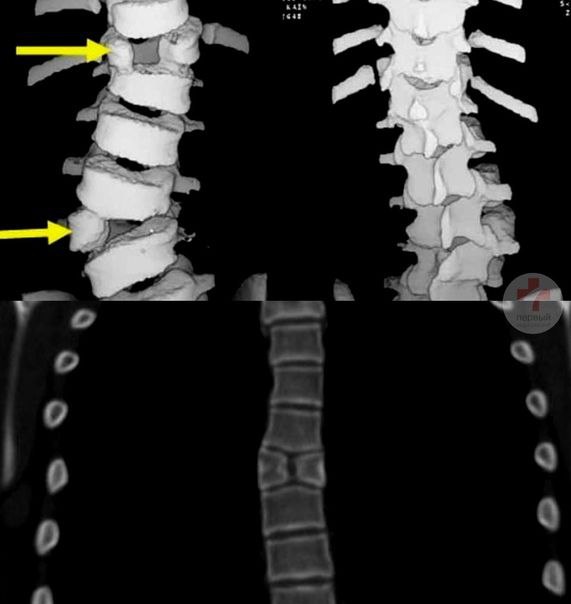

Стертый позвонок

Стертый позвонок 107 фотографий